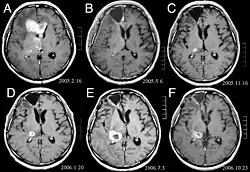

Na -MRI ukazuje intrakraniální tumor jako masivní lézi, která se po použití kontrastní látky může stát více luminiscenční. Vždy však dojde k anomálii signálu -Magnetická rezonance, která indikuje přítomnost neoplazie nebo vazogenního edému. Obvykle zvýšená luminiscence (zesílení kontrastu) svědčí pro nádor vyššího stupně malignity. Pro glioblastom je charakteristický kontrastní prstenec, jehož luminiscenční část odpovídá vitální části maligního nádoru a tmavší -hypointense oblast odpovídající nekróze tkáně.

Typicky se u pacientů s anaplastickým astrocytomem objevují epileptické záchvaty, fokální neurologické deficity, bolesti hlavy a změny osobnosti. Průměrný věk pacientů je 45 let. Magnetická rezonance obecně ukazuje masivní lézi se zvýšeným kontrastním signálem, který může být i slabší. Diagnóza je histologickým vyšetřením léze biopsií nebo chirurgickou resekcí.

Pacienti trpí řadou charakteristických symptomů fokální nebo multifokální masivní léze. MRI obvykle ukazuje nádory s homogenním zvýšením kontrastu v hluboké periventrikulární bílé hmotě. Pro pacienty s oslabeným imunitním systémem je typická multifokalita a nehomogenní zesílení. Analýza lymfomu CNS je mimořádně důležitá v diferenciální diagnostice neoplazie mozku. Je třeba poznamenat, že podávání kortikosteroidů může vést k úplnému vymizení zesílení, což ztěžuje diagnostiku lézí. V důsledku toho, má-li být lymfom CNS zvažován v diferenciální diagnóze, je třeba se kortikosteroidům vyhnout, pokud hromadný účinek nezpůsobí u pacienta závažný a bezprostřední problém.